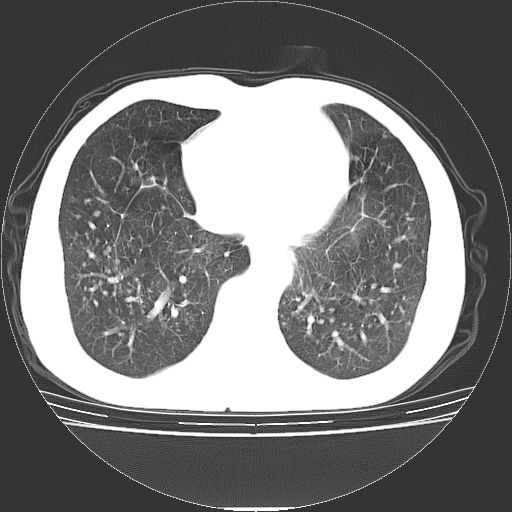

以下是引用yangyudong333在2008-4-29 5:38:00的发言:[br]比较典型的矽肺结节.支持[br]诊断依据:[br] 1.x线表现:[br] ①典型矽肺为多发直径 1~3mm 小结节,即矽结节,由胶原纤维和硅尘构成,可融合成团块,好发于上肺。[br] ②团块周围常有肺大泡。[br] ③胸内淋巴结增大、钙化。如肺门淋巴结呈蛋壳样钙化有助于与其他尘肺区别。[br] ④胸膜常广泛粘连、增厚。[br] 2.ct表现[br] ①两肺散在大小较为一致的小结节影,其密度较高,边界清楚。[br] ②小结节可融合为较大团块影,直径约 1cm ,甚至可达 10cm以上,易发生在上叶。[br] ③小结节周围常并有小叶中心气肿或弥漫性肺气肿。

以下是引用liuyue在2008-4-28 22:30:00的发言:[br]比较典型的矽肺结节.[br]请结合临床及化验除外矽肺合并肺结核之可能.